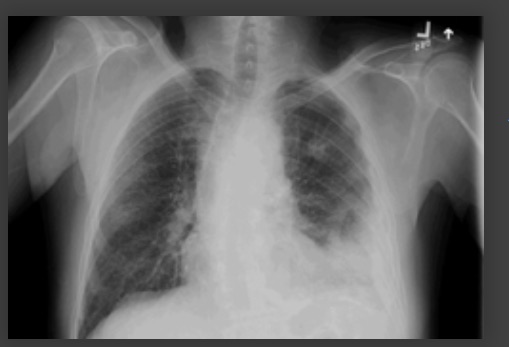

Derrame pleural no lado esquerdo

Da coleção do Dr. R Light. Usado com permissão